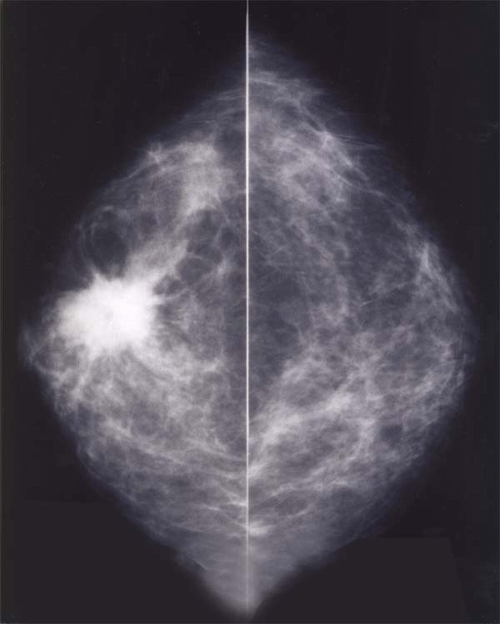

A. À¯¹æ ÃÔ¿µ¼ú

À¯¹æÁ¶Á÷¿¡ ´ëÇÑ x-¼± °Ë»ç¹æ¹ýÀÔ´Ï´Ù.

À¯¹æ¾ÏÀÇ °ËÁø¿¡ ÀÖ¾î À¯¹æ ÃÔ¿µ¼úÀº ÀϺΠÀ¯¹æ¾ÏÀÇ °æ¿ì µ¢¾î¸®°¡ ¸¸Á®Á®¼ Áø´ÜµÇ±â ÀÌÀü, (¾à 1-2³â Àü¿¡) À¯¹æ¾ÏÀ»

¹ß°ßÇÒ ¼ö ÀÖ¾î À¯¹æ¾ÏÀÇ Á¶±â¹ß°ß°ú Á¶±âÄ¡·á¿¡ Å« ¿ªÇÒÀ» ÇÕ´Ï´Ù.

»çÁøÀ» º¸¸é À¯¹æ Á¶Á÷Àº Èñ°Ô ³ªÅ¸³ª¸ç, Áö¹æ Á¶Á÷Àº °ËÀº»öÀ¸·Î ³ªÅ¸³³´Ï´Ù. ÀϹÝÀûÀ¸·Î ¿¬·ÉÀÌ Áõ°¡ÇÔ¿¡ µû¶ó Áö¹æÁ¶Á÷ÀÇ

¾çÀÌ Áõ°¡ÇÏ°Ô µÇ¾î Æó°æ±âÀÇ ¿©¼ºµé¿¡¼ ÂïÀº »çÁø¿¡¼´Â µ¢¾î¸® °°Àº Á¾±« À½¿µÀ» ½±°Ô ãÀ» ¼ö ÀÖ½À´Ï´Ù. ¹Ý¸é¿¡, ÀþÀº

¿©¼ºÀÇ »çÁø¿¡¼´Â Àü¹ÝÀûÀÎ À½¿µÀÌ À¯¹æ ½ÇÁúÁ¶Á÷ÀÇ Áõ°¡·Î µ¢¾î¸®ÀÇ À½¿µÀ» ã±â ¾î·Æ°Ô µË´Ï´Ù.

À¯¹æ¾ÏÀÇ »çÁø»ó ¼Ò°ßÀ» º¸¸é, ´ëü·Î µ¢¾î¸®(Á¾±«) ȤÀº ¹Ì¼¼ ¼®È¸À½¿µÀÇ ¾ç»óÀ¸·Î º¸ÀÔ´Ï´Ù.

µ¢¾î¸®´Â ¸ð¾çÀÌ ºÒ±ÔÄ¢ÇÏ°í °æ°è°¡ ÁöÀúºÐÇÑ ¸ð½ÀÀ» »çÁø»ó º¼ ¼ö ÀÖ½À´Ï´Ù.

À¯¹æ¾ÏÀÇ ¾à 4ºÐÀÇ1¿¡¼´Â ¹Ì¼¼ ¼®È¸À½¿µÀÌ º¸ÀÔ´Ï´Ù, ƯÈ÷ Á¶±â À¯¹æ¾ÏÀÇ °æ¿ì µ¢¾î¸®(Á¾±«)´Â ¸¸Á®ÁöÁö ¾Ê´Âµ¥ ¼®È¸¸¸

º¸ÀÌ´Â °æ¿ì°¡ ¸¹½À´Ï´Ù.